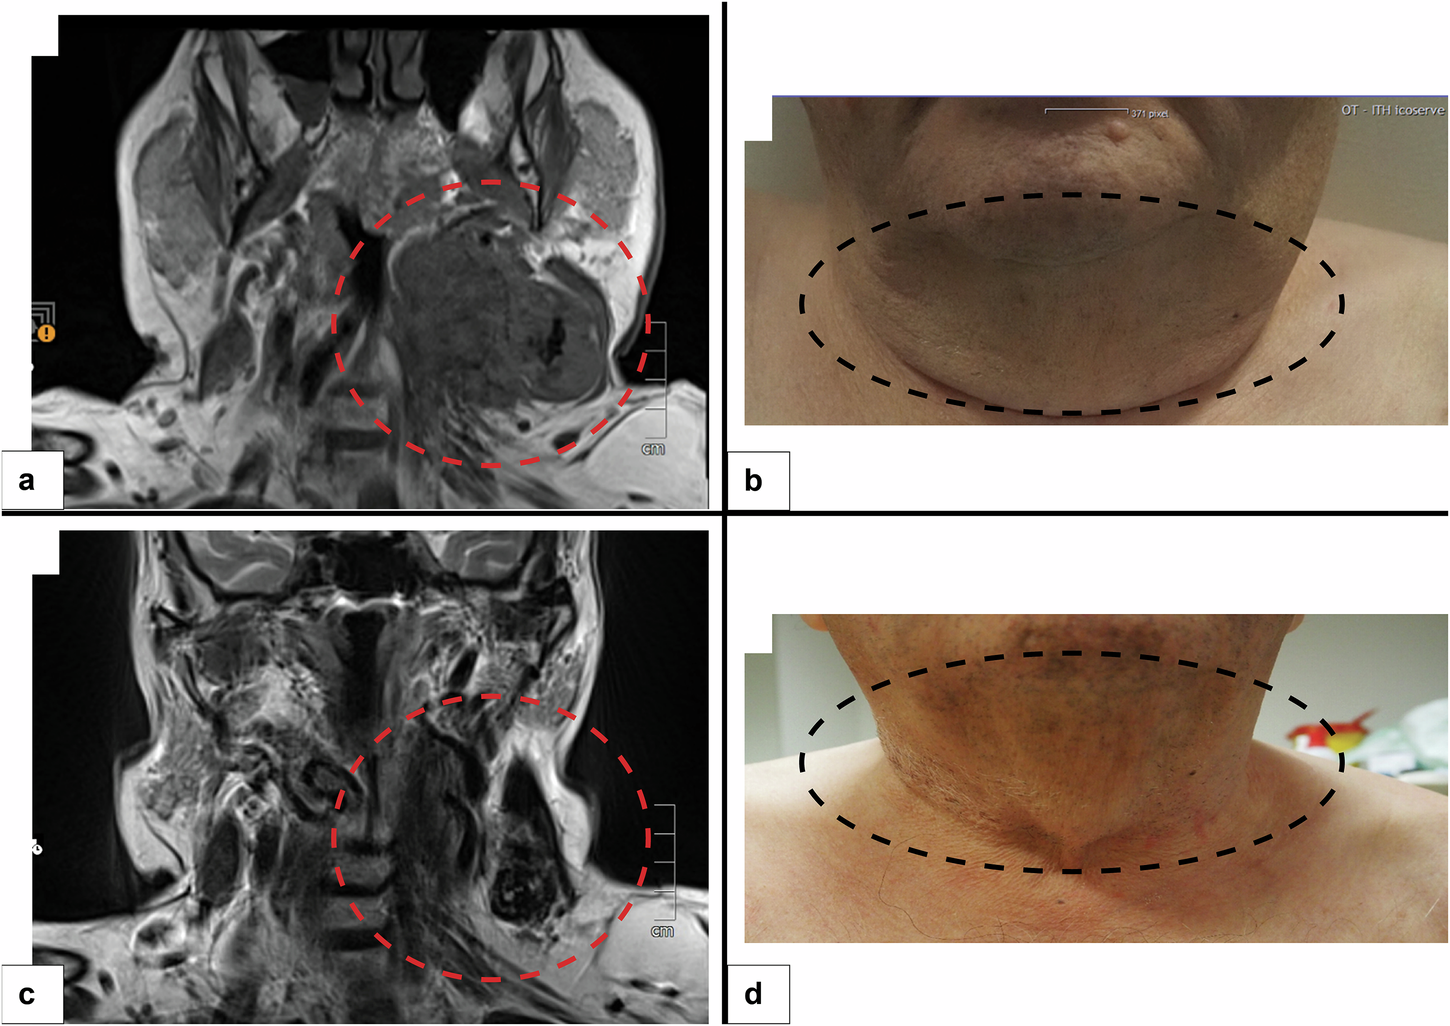

Fig. 2: Clinico-radiological correlation of the disease course.

a MRI of the tumor (coronal cut) before initiation of treatment with larotrectinib (tumor encircled). b Clinical picture of the patient’s neck before treatment initiation (tumor encircled). c MRI of the tumor (coronal cut) 2 months after treatment with larotrectinib (tumor encircled). d Clinical picture of the patient’s neck 3 weeks after treatment initiation (tumor encircled).